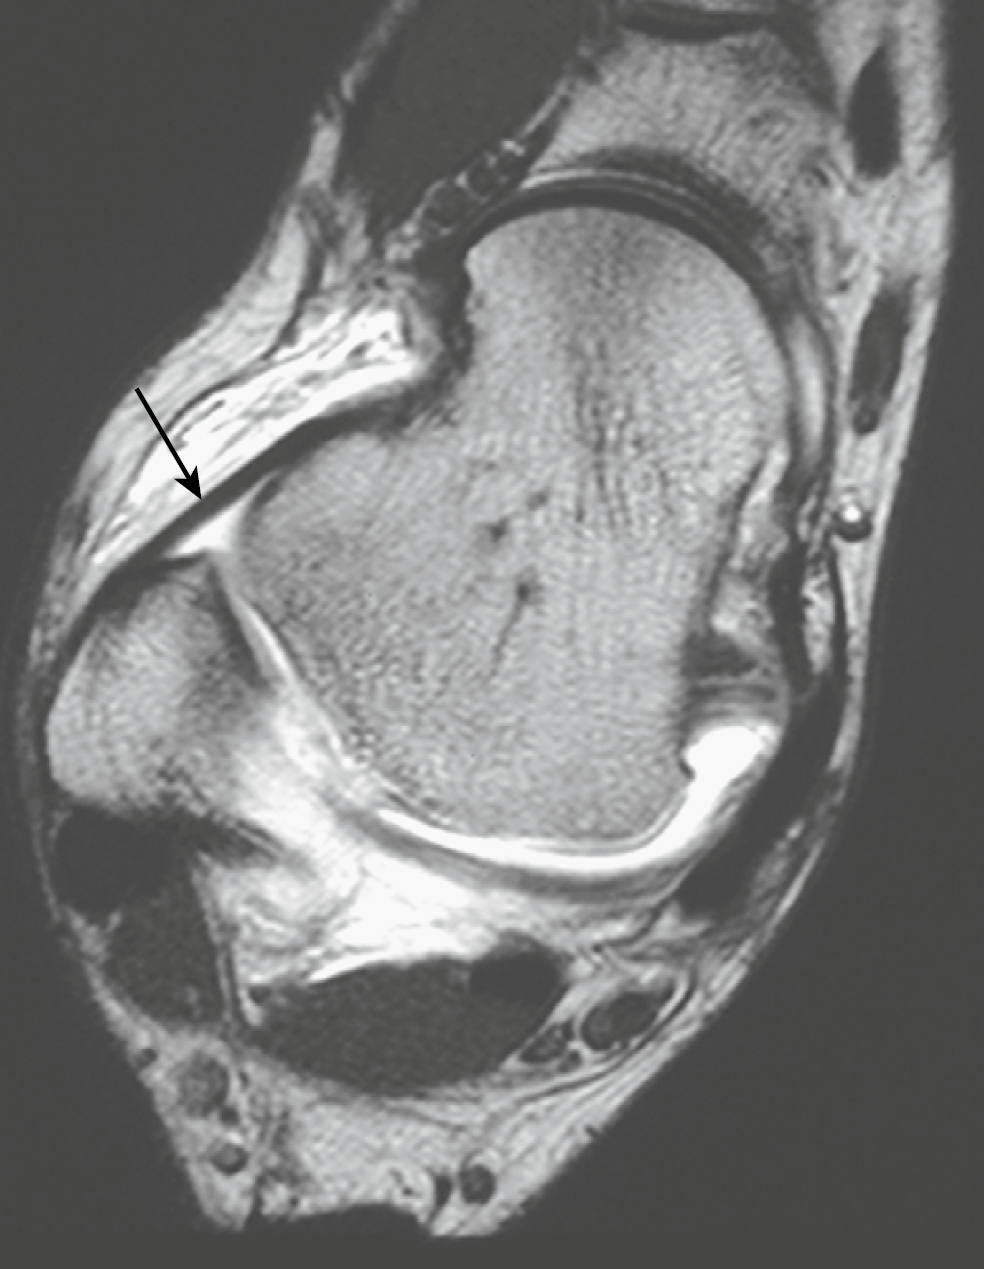

图1轴位T1加权的MR的关节造影图像:一个正常的、低信号强度距腓前韧带(箭头)